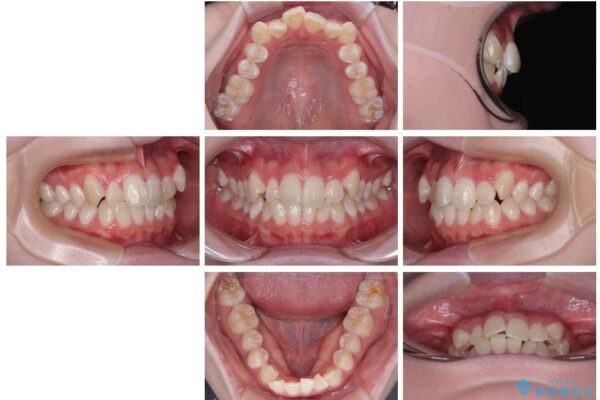

「前歯のデコボコ(叢生)をきれいに整えたい」とのことでご来院されました。

治療前

• 【モニター】前歯のデコボコをスッキリ解消!目立ちにくいワイヤー矯正でスピーディに治療完了 治療前画像